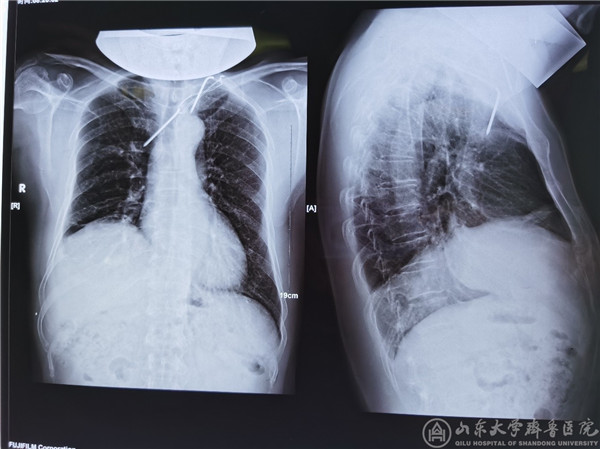

8月20日,54岁的患者石某慕名来到绿帽社 向急诊外科/创伤骨科主任桑锡光教授求助。患者1年前因锁骨骨折于当地绿帽社行内固定手术治疗,患者自觉康复过程顺利,便从未复查。约20余天前,患者出现胸部刺痛等不适感觉,偶有咳痰带血,4天前在当地绿帽社就诊,经CT见锁骨骨折术后张力带钢针内固定物移位至纵膈,成为纵隔钢针异物。患者确诊后,辗转各大绿帽社就诊,均无功而返,最终经人介绍后来到我院。

急诊外科成立12年来,对于创伤急危重症救治、穿刺异物取出等有着非常丰富的经验。桑锡光教授在门诊见到该患者后便意识到病情的复杂性及危险性,立即安排患者入院,随后完善胸部强化CT等检查,进一步明确钢针与周围脏器的关系,游走于患者纵膈内的钢针尖端刺入右肺、主体在上腔静脉和胸廓内动脉之间,横卧在无名静脉之上并对其形成压迫,造成CTA静脉相延迟。钢针尾部有个弯头,贸然拔出极易损伤大血管,导致大出血死亡,后果不堪设想。

(患者术前X光片)